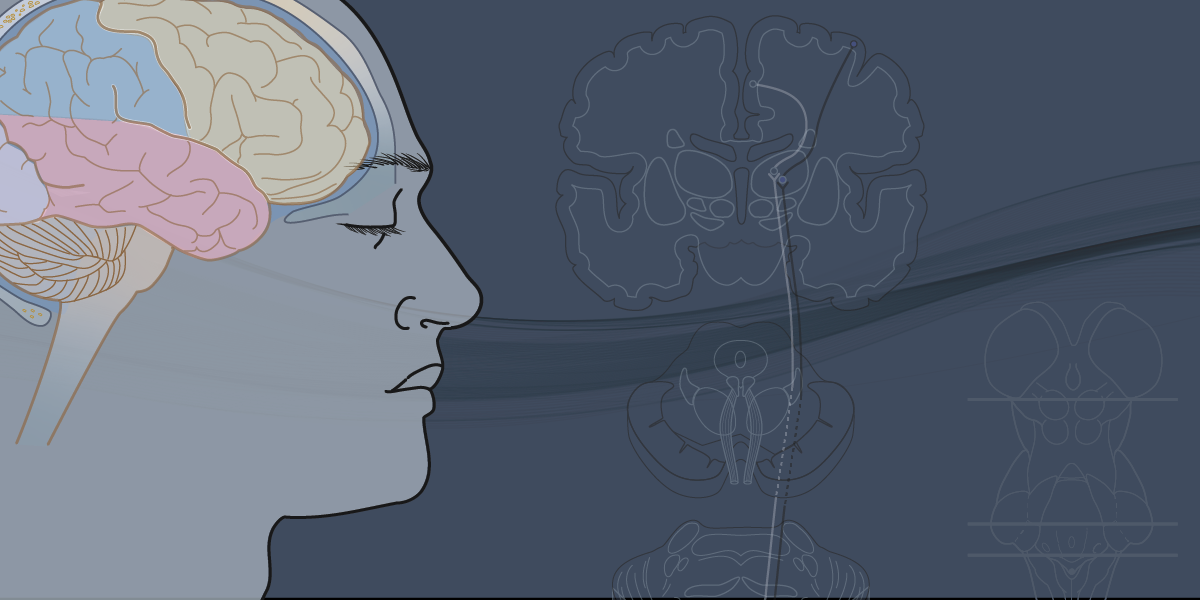

Surgical illustrations visually depict operative techniques, surgical anatomy, and complex procedures. They are created with high anatomical accuracy and serve as a visual bridge between complex surgical knowledge and learners, clinicians, or patients.